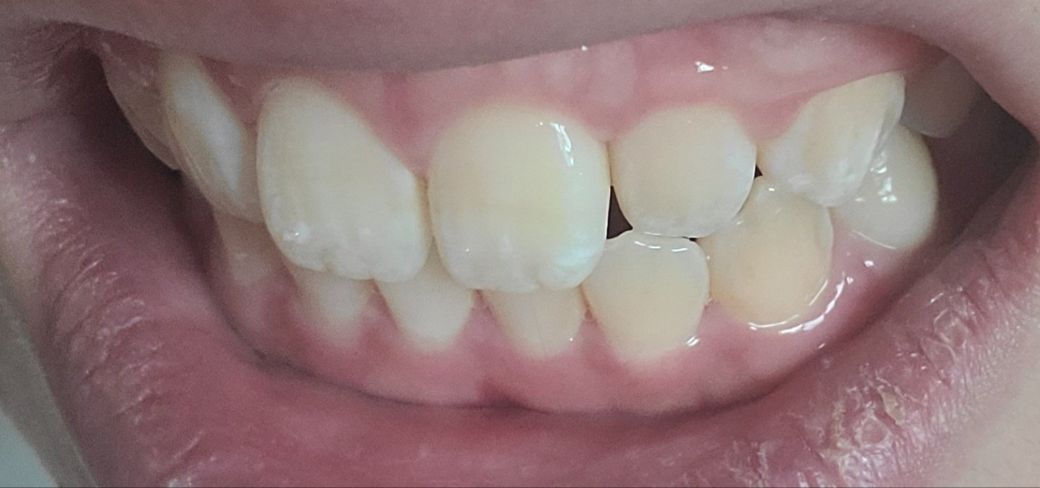

두번째 앞니사진